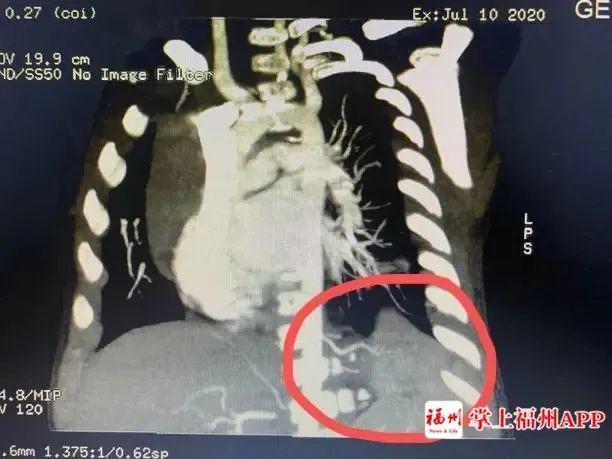

一个咳嗽这么难治愈吗?经过福建省福州儿童医院肺部CT检查,真相是小明的身体里“多了个肺”!!

医学上称为“肺隔离症”。

肺隔离症是一种先天性肺畸形,临床少见,其发病率约占先天性肺畸形的0.15% ~6.45%,一般无明显临床症状,多在合并肺内感染时与正常肺组织相通出现咳嗽、咳痰、咯血等症状,且反复发作,临床易误诊。

●其实质是由异常血管供血的肺囊肿症

●常与正常肺分开存在,有单独体循环血液供应

●增强CT结合三维血管重建发现异常供血可以确诊